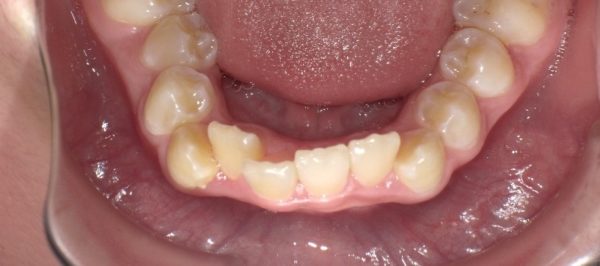

では、顎の成長の遅延はどこで判断するでしょうか?

→それは、上顎4前歯部の生え変わりで判断します。

前歯が、重なっている場合は、顎の横幅が狭いことになり、顎の成長が、遅延していると判断します。大切なのは、「なぜ?」顎の遅れが生じたのか?が大切です。